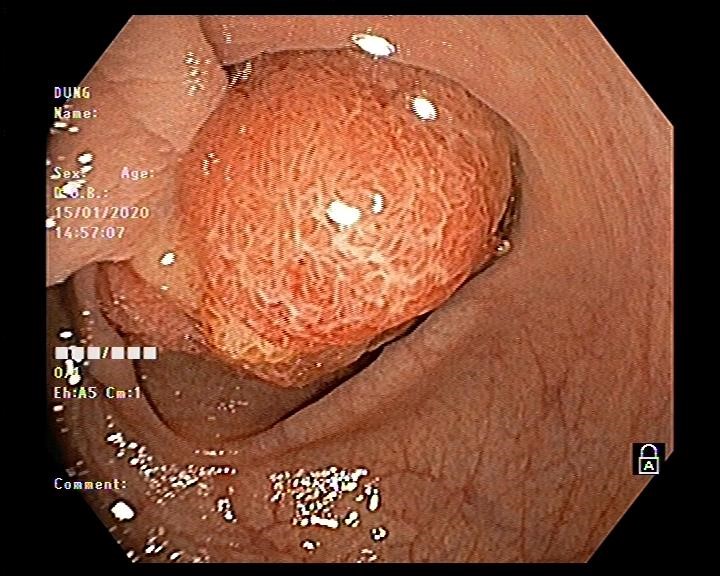

Hình ảnh nội soi đại tràng cắt polyp

Bệnh nhân nam 61 tuổi đi khám bệnh tại Bệnh viện đa khoa tỉnh Hải Dương vì lý do đi ngoài ra máu. Bệnh nhân được bác sĩ khám và cho chỉ định nội soi đại tràng. Trong quá trình nội soi phát hiện ở đại tràng sigma có 01 polyp lớn khoảng 2,5 cm có cuống lớn và dài. Bệnh nhân có chỉ định cắt polyp phòng ngừa nguy cơ polyp ung thư hóa.

Vấn đề đặt ra là với kích thước và tính chất polyp như vậy thì có khả năng polyp được nuôi bằng mạch máu lớn, nếu chỉ cắt đốt bằng phương pháp thông thường thì nguy cơ xuất huyết ồ ạt sẽ rất cao. Do đó bác sĩ nội soi Ths Vũ Thanh Tùng quyết định sử dụng vòng Endoloop để thắt cuống polyp trước khi tiến hành cắt đốt. Thủ thuật diễn ra thuận lợi, nhanh gọn trong vòng 10-15 phút và không xảy ra tai biến dù là polyp này được nuôi bằng mạch máu lớn.